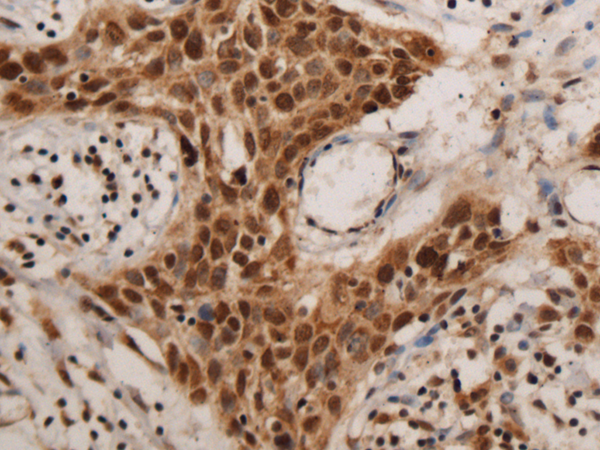

Applications:

ELISA, IHC

IHC positive control:

Human colorectal cancer and Human esophagus cancer

IHC Recommend dilution:

100-300